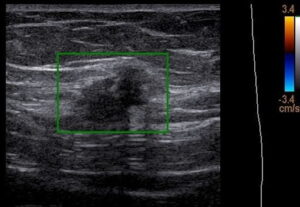

Ultrassom transvaginal com preparo intestinal demonstrando um endometrioma no ovário direito.